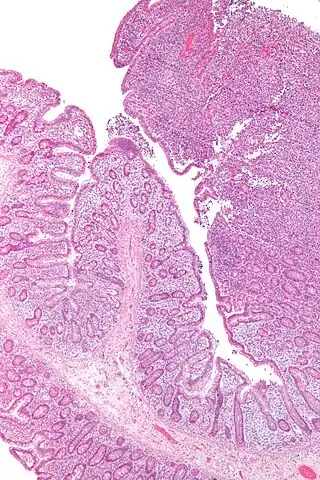

![]() Una micrografía del linfoma de células T asociado a enteropatía. | ||